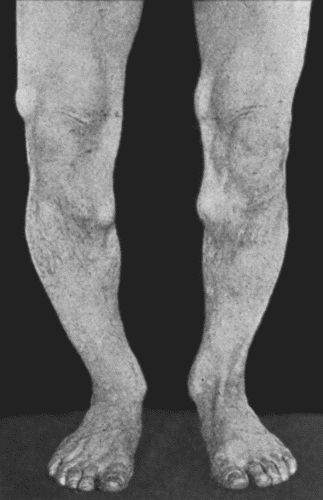

164.Charcot's Disease of both Ankles: front view 535

165.Charcot's Disease of both Ankles: back view 536